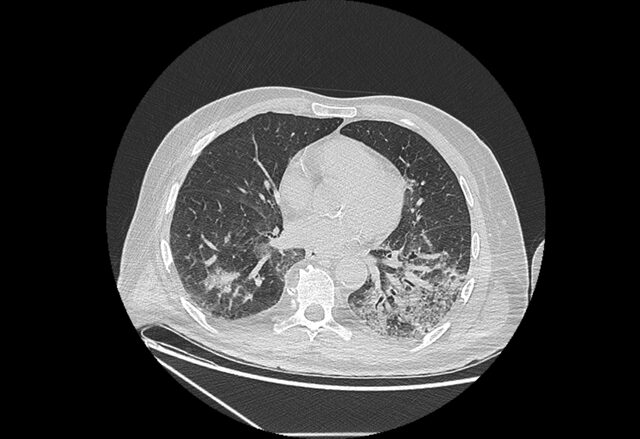

Kliniğe yeni başvuran bir hastanın, 5 Ağustos'ta çekilen tomografi görüntülerindeki tipik koronavirüs görüntülerinin olduğunu ifade eden Karalezli, hastanın bir hafta içerisindeki tomografi görüntüsünde ciddi değişiklik olduğunu ve enfeksiyonun çok arttığını söyledi.